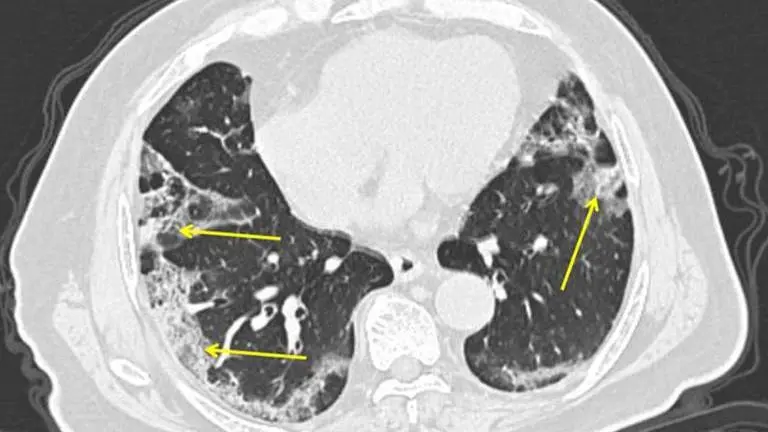

Doctors at New York’s Mount Sinai Health System analyzed 121 chest CT scans shared by colleagues in China and spotted something unusual.

Healthy lungs look mostly black on medical scans because they’re full of air. An early infection with bacterial pneumonia tends to show up as a white blotch in one section of one lung. Pneumonia caused by a virus can show up as hazy patches that go by a weird name — “ground-glass opacities.”

In people who get COVID-19 pneumonia, that haze tends to cluster on the outside edge of both lungs, by the ribs, a distinctive pattern, said Dr. Adam Bernheim, a radiologist at Mount Sinai.

As infection worsens, the haze forms rounder clusters and gradually turns more white as the air sacs become increasingly clogged.